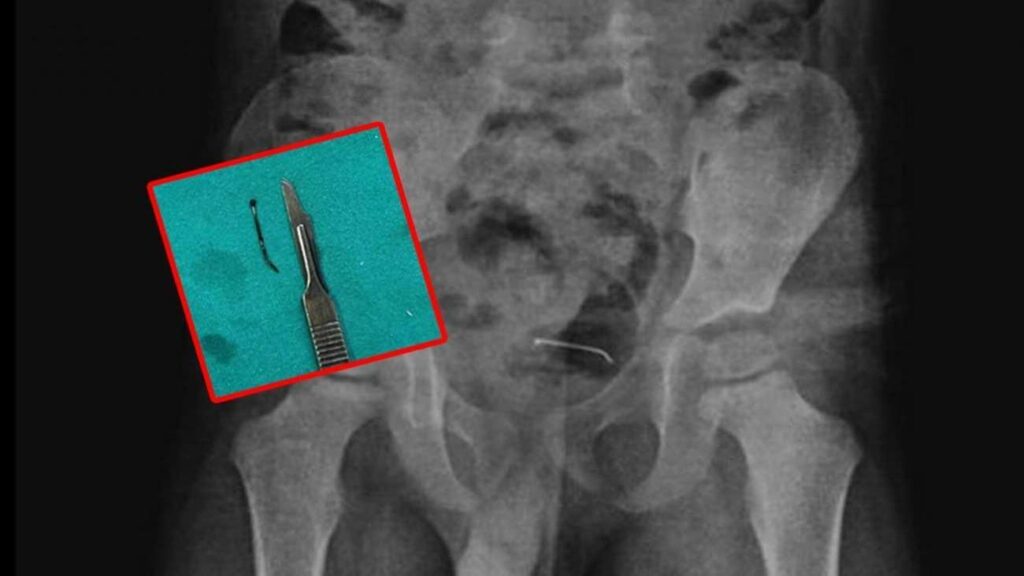

Bitlis’te oyun oynarken toplu iğne yutan 5 yaşındaki çocuk “yabancı husus yutma” münasebeti ile ailesi tarafından hastaneye götürüldü. Tabiplerin incelemelerine karşın sonuç alamayan aile meskene geri döndü. 9 ay sonra şiddetli karın ağrısı yaşayan çocuk tekrar hastaneye götürüldü. Yapılan tetkikler sonucunda çocuğun mesane duvarında görülen ve toplu iğne olduğu tespit edilen yabancı husus başarılı bir cerrahi operasyonla alındı.

5 yaşındaki çocuğa yapılan tetkikler sonucunda, şiddetli karın ağrısına neden olan durumun mesane duvarına yapışan yabancı unsur olduğu tespit edildi. Küçük çocuğun yuttuğu 3 santimetre uzunluğundaki toplu iğne başarılı bir operasyonla alındı.

Kamçı, yabancı cismin bedenden olağan yollarla atılamadığını belirterek, “Bunun üzerine ameliyat kararı aldık. Ameliyatta cismin mesane duvarına yapıştığını gördük. Cerrahi operasyonla 3 santimetre civarındaki toplu iğneyi çıkardık. Hastayı birkaç gün takipte tuttuk. Genel sıhhat durumu düzgün olan hastamızı taburcu ettik.” ifadelerini kullandı.